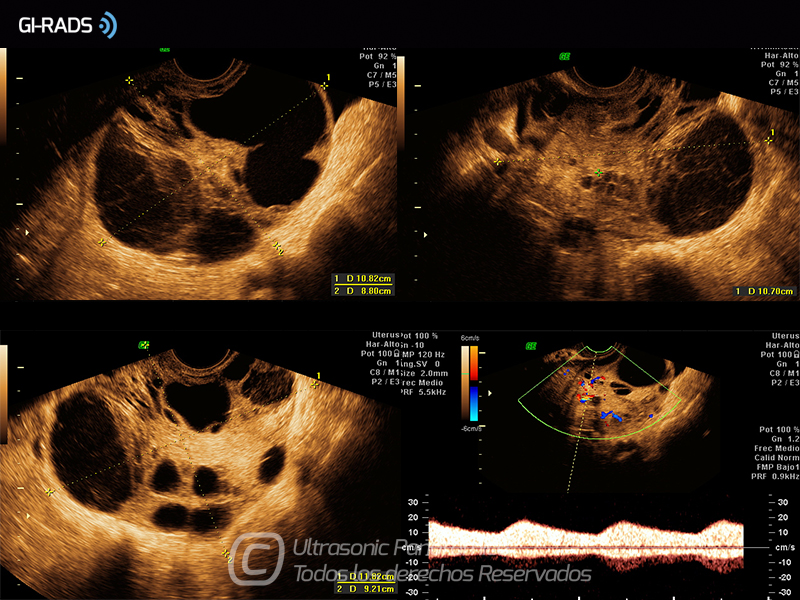

Cáncer Anexial – Áreas Sólidas

• Cáncer Anexial – Áreas Sólidas

• Cáncer Anexial – Flujo Interno

• Cáncer Anexial – Flujo Abundante

• Cáncer Anexial – Baja Resistencia